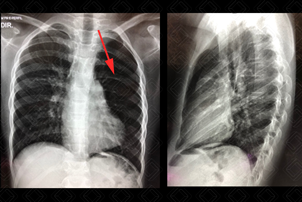

Texto alternativo para a imagem Figura 1. Créditos: Dra. Elazir Mota - Rio de Janeiro/RJ

Descrição da figura 1: Trata-se de um caso de hipertransparência pulmonar unilateral na radiografia de tórax. Observe que a transparência pulmonar esquerda é maior que a direita (ou seja, o pulmão esquerdo encontra-se mais “preto” que o contralateral) – seta vermelha. Foram afastadas as outras possibilidades diagnósticas e confirmada a síndrome de Poland.

Síndrome de Poland: Síndrome congênita caracterizada pela agenesia unilateral da musculatura peitoral maior e/ou menor. Trata-se de uma das causas de hemitórax hiperluscente unilateral.

• Radiografia de tórax : A síndrome de Poland trata-se de uma das causas de hemitórax hiperluscente unilateral. É necessário excluir as outras causas de hiperluscência na radiografia aliado a um bom exame clínico do paciente (figura 1);